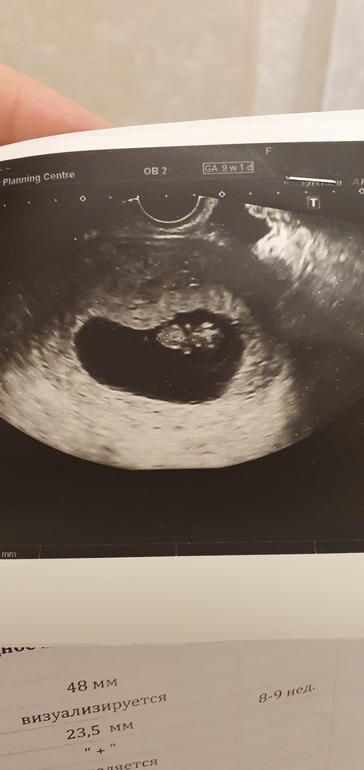

УЗИ, КТГ, доплерБлин, смотрю, всем на УЗИ говорят, по какой стенке прикрепление, мне ни на одном не сказали( по фото это можно определить?

На бумажке должно быть написано по узи: локализация плаценты по передней , задней, дне матки , справа , слева. Должно быть подчеркнуто как именно у вас!

Свет должны были сказать на Узи, по фото не определишь. Мне и в 7 недель и в 9 сказали по передней:) поэтому ожидаю ранний и большой пуз😁